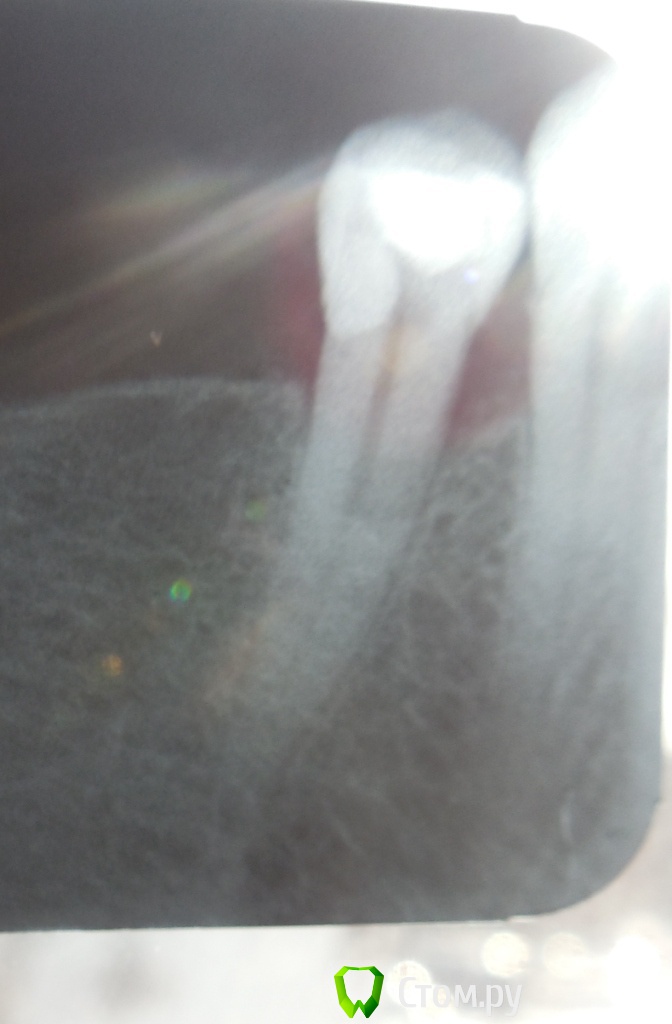

Л-Ф Опубликовано 2 апреля, 2014 Автор Поделиться Опубликовано 2 апреля, 2014 (изменено) У Вас должны быть еще снимки, после удаления нерваК сожалению,ни ДО ни ПОСЛЕ мне не делали снимки.Это я уже в платной сегодня сделала.Сейчас стоит временная,белая пломбаЭти снимки с временной пломбойДобавлю,что зуб немножко подвижный...немногоЕще вопрос.Удален ли у меня нерв полностью?И в сом низу зуба очертания какие то....может там воспаление? или мне кажется Изменено 2 апреля, 2014 пользователем Л-Ф Ссылка на комментарий

Гарриевич Опубликовано 2 апреля, 2014 Поделиться Опубликовано 2 апреля, 2014 Синяк у Вас, это гематома после укола, такое бывает... пройдет. Корневой канал еще не запдомбирован, поэтому сказать, что то о качестве не могу. Един ственный момент который сильно смущает это отсутствие снимков в процессе работы Ссылка на комментарий